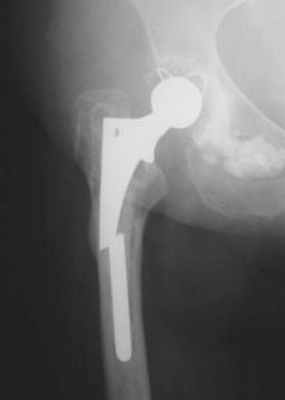

Классические эндопротезы тазобедренного сустава (протез с прямой ножкой) отличаются от замены только суставной поверхности тем, что имплантат устанавливают в бедренной кости. Для того, чтобы надёжно закрепить стержень (ножку) протеза, при тотальном эндопротезировании удаляют головку бедренной кости, а также отдельные части шейки бедра. Таким образом теряются костные структуры для ревизионного вмешательства.

Расположение поверхностного эндопротеза тазобедренного сустава. Операция по методу McMinn © Implantcast

После операции по поверхностному эндопротезированию полные нагрузки как правило разрешены и рекомендованы уже на следующий день. Исходя из нашего долголетнего опыта более длительный процесс восстановления не целесообразен. Пациенты могут совершать нагрузки на тазобедренный сустав при условии использования подлокотных костылей.